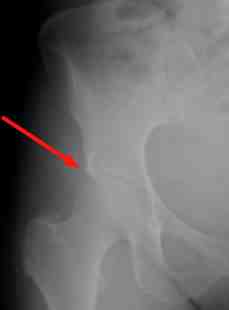

A pincer deformity is a not uncommon cause of stiffness and ultimately hip and thigh pain; the x-ray above reveals a very small deformity, but enough to be disturbing.

Xrays

which I now deemed to be necessary show a very small pincer deformity,

entirely consistent with the presentation of very limited and flexion

and adduction of the hip. It's not a very good quality film.